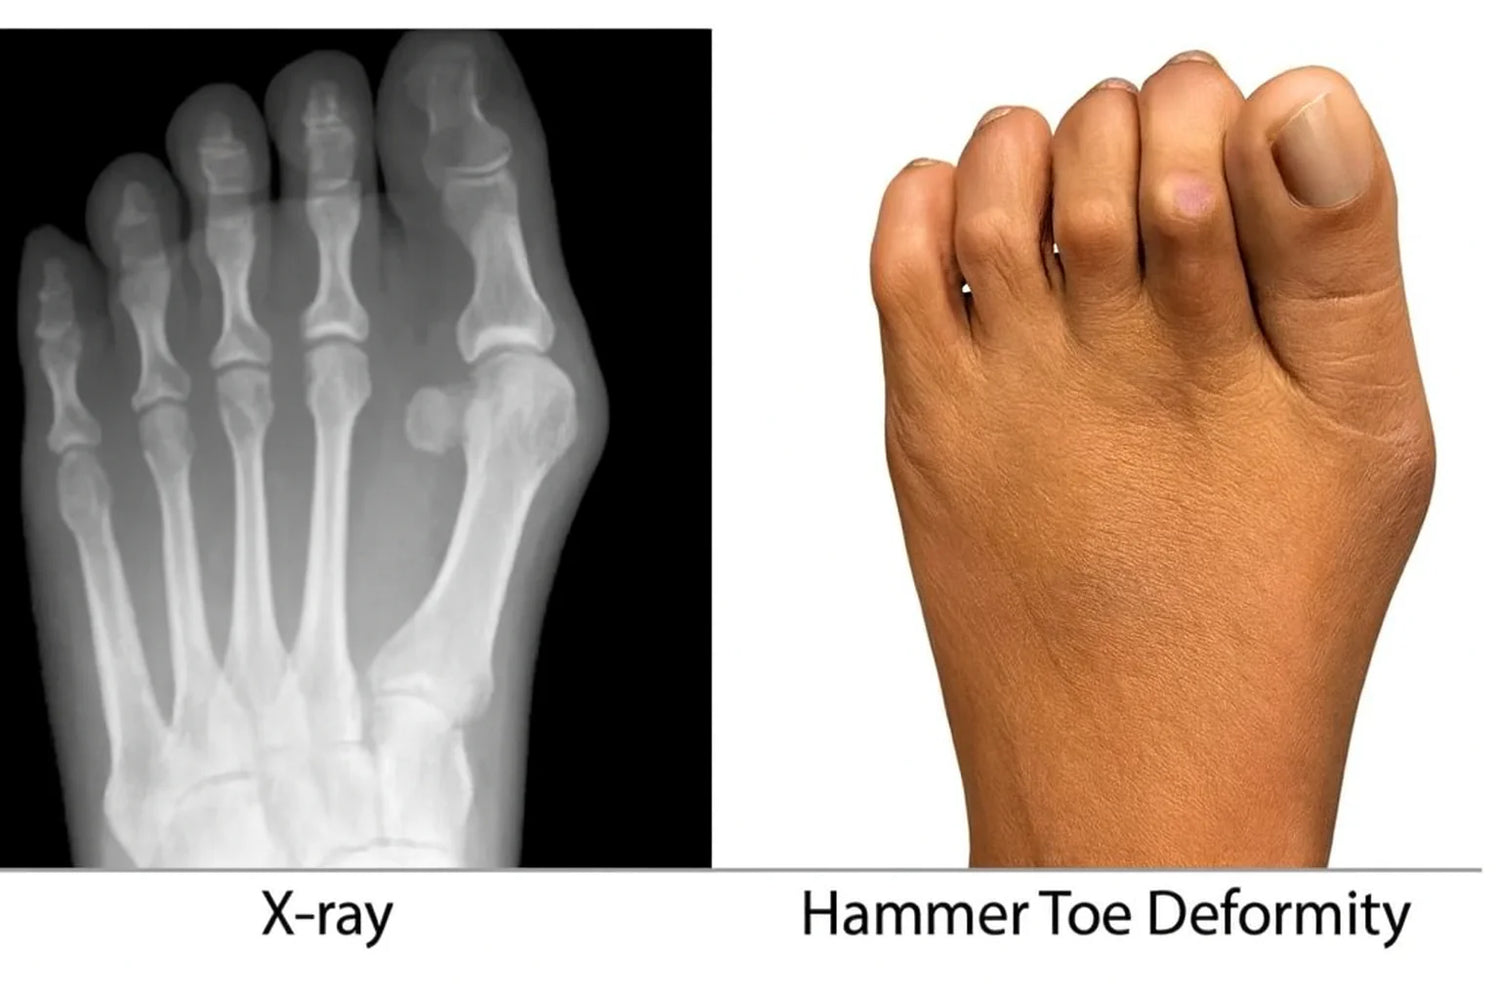

That painful, crooked toe isn't just a joint that's stuck in an awkward position.

What’s really happening is your toe is buckling at the middle joint, forcing it into a bent, hammer-like shape.

Its natural position should be flat and straight, just like how babies’ feet look when they’re born.